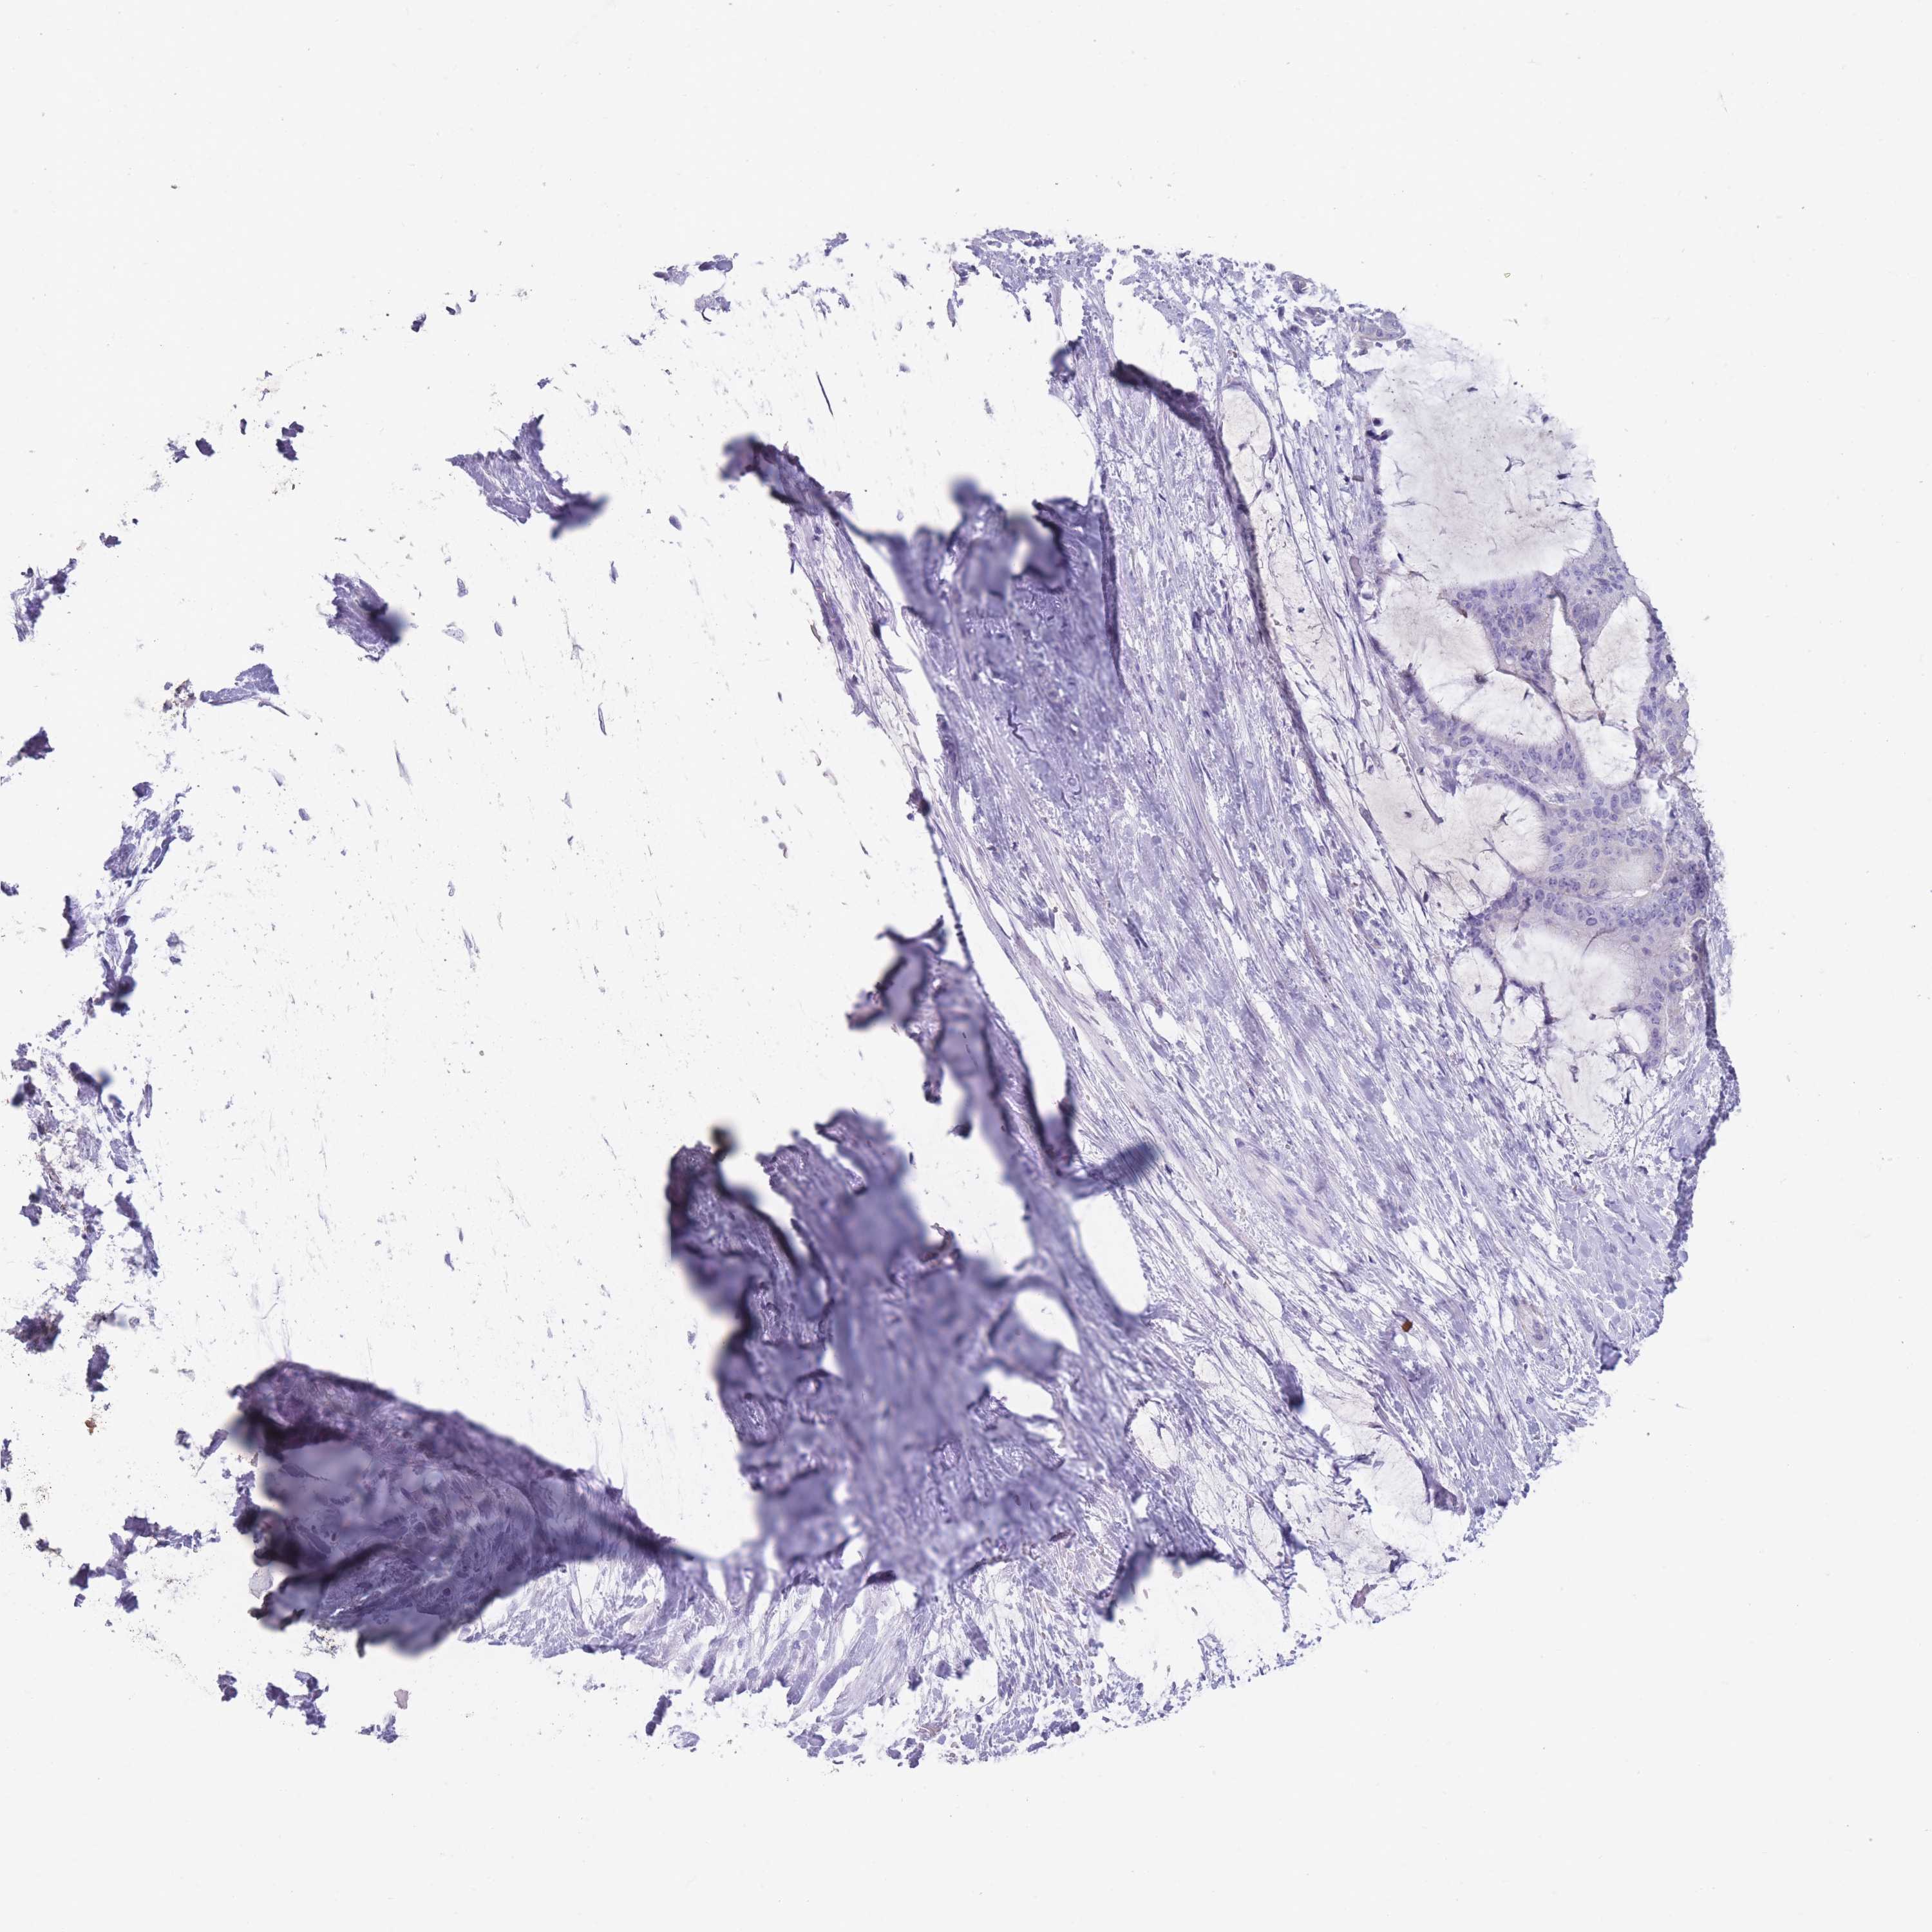

LIVER CANCER - Protein expressioni

A mouse-over function shows sample information and annotation data. Click on an image to view it in a full screen mode. Samples can be filtered based on level of antibody staining by selecting one or several of the following categories: high, medium, low and not detected. The assay and annotation is described here.

Note that samples used for immunohistochemistry by the Human Protein Atlas do not correspond to samples in the TCGA dataset.

Antibody stainingi

Antibody staining in the annotated cell types in the current human tissue is reported as not detected, low, medium, or high, based on conventional immunohistochemistry profiling in selected tissues. This score is based on the combination of the staining intensity and fraction of stained cells.

Each image is clickable and will lead to virtual microscopy that enables deeper exploration of all samples and also displays staining intensity scores, fraction scores and subcellular localization as well as patient and tissue information for each sample.

Antibody HPA048489

Staining

High

Medium

Low

Not detected

Intensity

Strong

Moderate

Weak

Negative

Quantity

>75%

75%-25%

<25%

None

Location

Nuclear

Cytoplasmic/membranous

Cytoplasmic/membranous,nuclear

Cholangiocarcinoma

Carcinoma, Hepatocellular, NOS